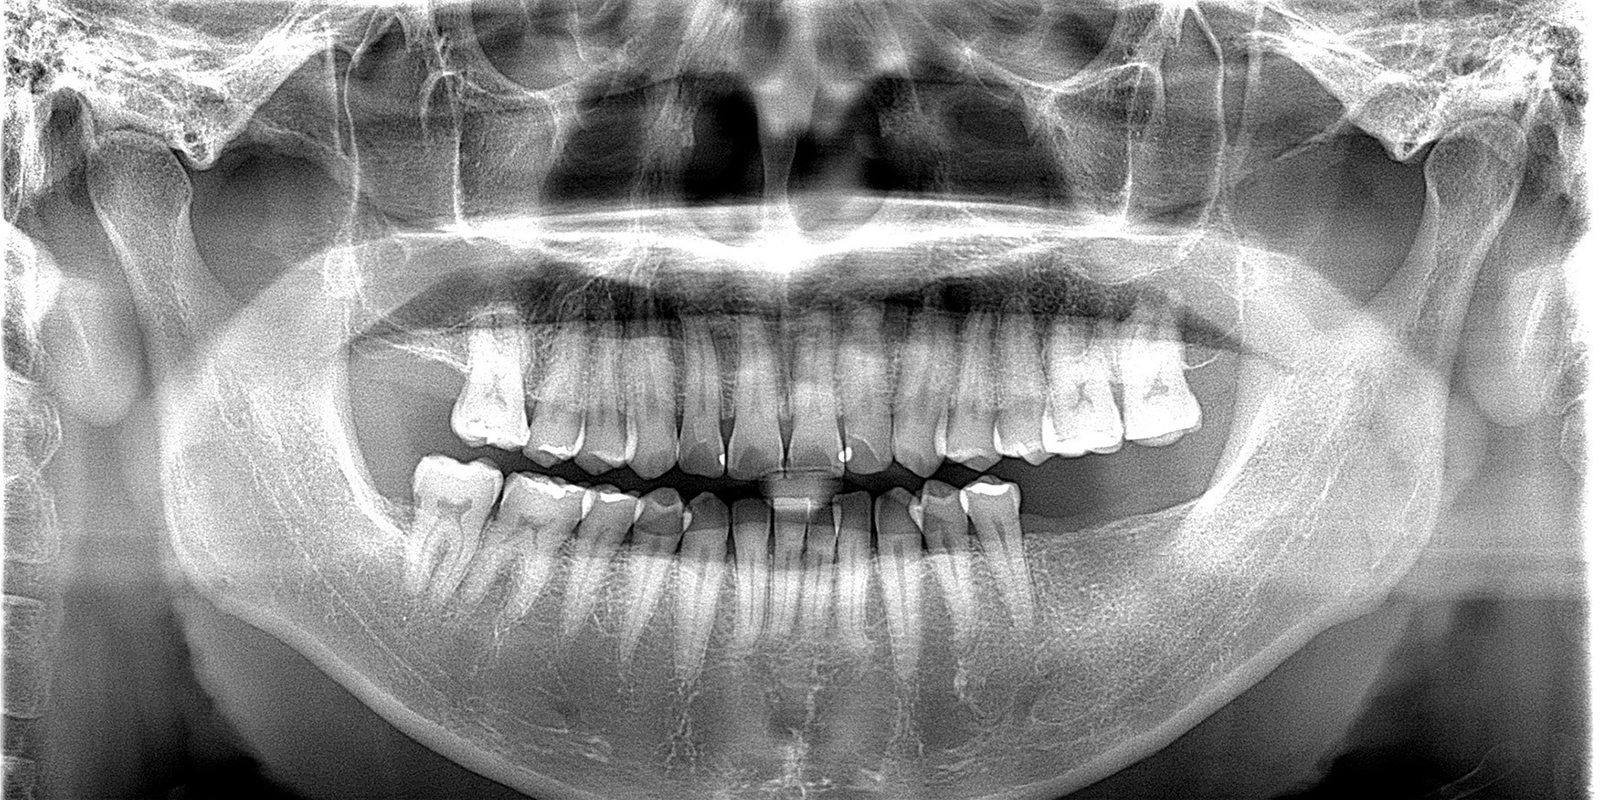

左下インプラント埋入のケース

このケースを例に一般的なインプラント埋入(一次オペ)の手順についてご説明致します。